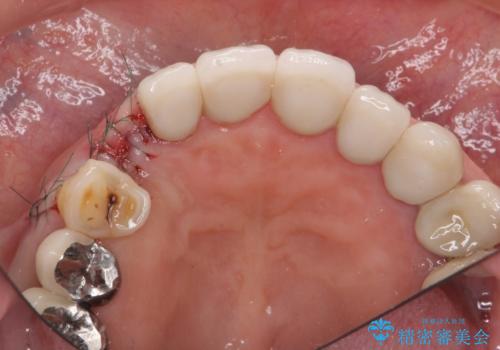

クラウン下に再発した深い虫歯 インプラントによる機能回復

前歯のインプラントを仕上げるには骨や歯ぐきの条件を整えることが肝要です。

ブリッジや歯の挺出を行い保存する提案も行いましたが、短期間の定期的な通院が難しくインプラントによる少ない回数での治療を希望されました。